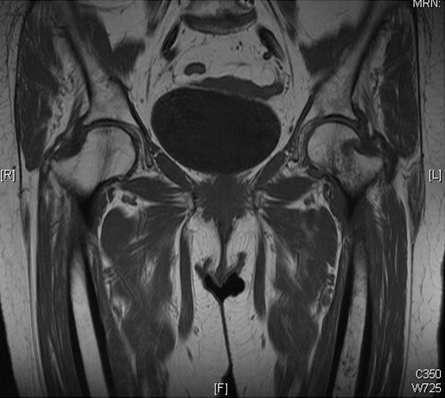

Outras investigações